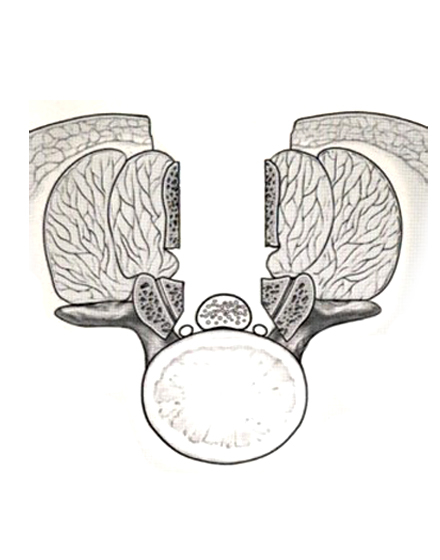

腰椎棘突起縦割式椎弓切除術

適応となる疾患:腰部脊柱管狭窄症、腰椎変性すべり症など

腰椎後方(背中)から椎弓、肥厚した黄色靭帯を切除し、硬膜管(馬尾神経の通っている管)の圧迫を解除します。棘突起を縦割することで腰背筋を骨から切離せず温存して、余分な組織のみ切除する低侵襲な手術を行います。従来の手術に比べ、術後の腰痛が軽度です。手術時間は1時間くらいで翌日から歩行が許可されます。入院期間は通常10~14日ぐらいになります。